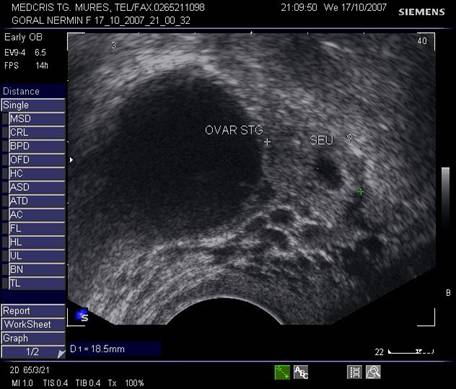

Fig nr 55 Langa ovarul stang, o formatiune ovalara ( intre calipere ) de 18 mm, cu ecou hipoecogenic central, la 6 sapt.de amnoree